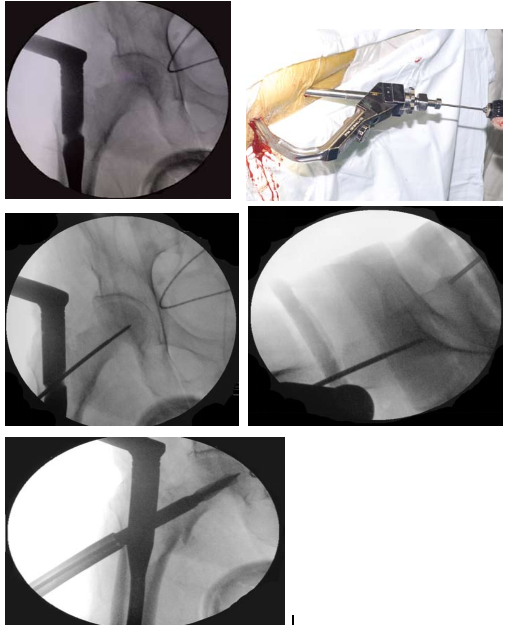

二 股骨粗隆间骨折的治疗首选股骨近端髓内钉固定(PFNA/Intertan)

髓内固定属于中心性固定不需要对内侧骨块解剖复位固定,不干预内侧的生物学环境,自然增加了骨折的愈合率。因此,髓内固定适于任何类型的骨折固定,特别是在不稳定型骨

折固定中表现优异。